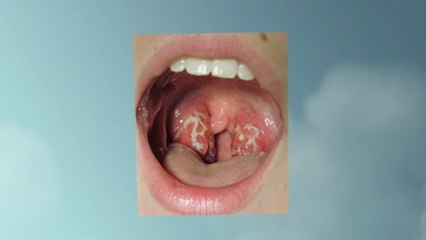

- Tonsil Stones Treatmentbr br Here's Your Chance to Get Rid of Tonsil Stones FOREVER with a Natural,br Simple Guide That Will Work.